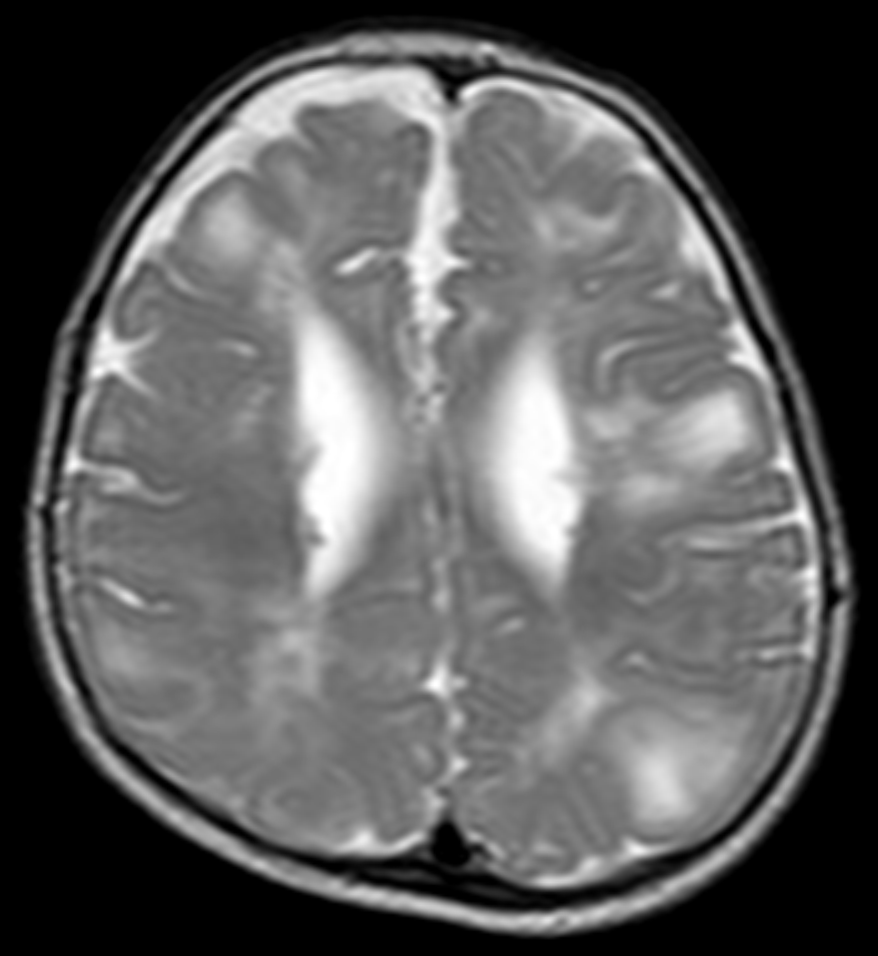

결절성 경화증(TSC)이 뇌에 영향을 미쳐 나타나는 신경학적 증상으로는 발작, 지적 장애, 발달 지연, 행동 문제 등이 있다.[4]결절성 경화증과 관련된 뇌 종양은 세 가지 유형이 있다.[4]

- 거대 세포 별아교세포종: 성장하여 뇌척수액 흐름을 막아 뇌실 확장을 일으켜 두통과 구토를 유발한다.

- 피질 결절: 질병의 이름이 여기서 유래되었다.

- 뇌실하 결절: 뇌실 벽에서 형성된다.

결절은 전형적으로 삼각형 모양이며, 꼭짓점이 뇌실을 향하고 있다. 자기 공명 영상(MRI)에서 TSC 환자는 비정상적인 뉴런 이동과 일치하는 다른 징후를 보일 수 있다. 뇌실하 결절은 시간이 지나면서 석회화되는 경향이 있다. 시간이 지남에 따라 현저하게 조영 증강되고 커지는 결절은 뇌실하 거대 세포 별아교세포종으로의 변형을 의심해야 하며, 이는 전형적으로 몬로공 부위에서 발생하여 폐쇄성 수두증이 발생할 위험이 있다.[4]

뇌 MRI를 통해 뇌 결절, 뇌실막하 결절, 뇌실막하 거대세포 별아교세포종 등을 확인할 수 있다.[21] 뇌파 검사(EEG)를 통해서는 뇌전증 여부를 확인하고, 발작 유형을 평가한다.[21] 복부 CT 또는 MRI를 통해 신장 혈관근지방종, 신장 낭종 등을 확인할 수 있다.[6] 고해상도 흉부 CT (HRCT)를 통해 폐 림프관평활근종증 여부를 확인할 수 있는데, 이는 주로 성인 여성에게서 나타난다.[7] 심장 초음파 검사를 통해서는 심장 횡문근종 여부를 확인할 수 있으며, 주로 영유아에게서 발견된다.[8] 안과 검진을 통해서는 망막 과오종 등을 확인할 수 있고[10], 피부과 진찰을 통해서는 피부 병변을 확인한다.[21]

자기 공명 영상(MRI)에서 TSC 환자는 T2WI에서 고신호 강도를 보이는 방사형 백질 경로 및 이소성 회백질과 같은 비정상적인 뉴런 이동과 일치하는 다른 징후를 보일 수 있다. 뇌실하 결절은 비정상적이고 부어오른 신경교 세포와 신경교 또는 뉴런 기원이 불확실한 기괴한 다핵 세포로 구성되며, 신경 조직은 존재하지 않는다. 이 결절은 환자가 나이가 들면서 석회화되는 경향이 있다. 시간이 지남에 따라 현저하게 조영 증강되고 커지는 결절은 뇌실하 거대 세포 별아교세포종으로의 변형을 의심해야 하며, 이는 전형적으로 몬로공 부위에서 발생하여 폐쇄성 수두증이 발생할 위험이 있다.

- 뇌 MRI를 촬영하여 결절, 상의하 결절(SEN) 및 상의하 거대 세포 성상 세포종(SEGA)을 확인한다.